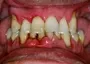

Periodontal Treatment

What causes Periodontal disease?

Periodontal (gum and bone) disease is an infection caused by bacteria. In about a days time, mouth bacteria multiply and form a sticky, almost invisible film on the teeth called plaque. Plaque that is not removed by regular brushing and flossing can harden into calculus (tartar). In some cases the plaque and calculus cause the gums to become red and inflamed and may bleed when brushing. This condition is called gingivitis. Over time, toxins in plaque can cause the tooth’s supporting tissue and bone to be destroyed, forming a hidden pocket between the tooth and gum. Your dentist and hygienist will use a special periodontal probe to measure the depth of these hidden pockets. The depth of this pocket (bone loss), in conjunction with other clinical symptoms like bleeding is the main indicator for the presence of periodontitis.

Do you have periodontal disease?

If left untreated, periodontal disease can lead to bleeding, discomfort, receding gums and tooth loss. More than 50% of South Africans 30 years and older have gingivitis and more than 33% have periodontitis. Periodontal disease affects 3 out of 4 people at some point in life.

Periodontal Disease Treatment South Africa

Treatment of Periodontal disease